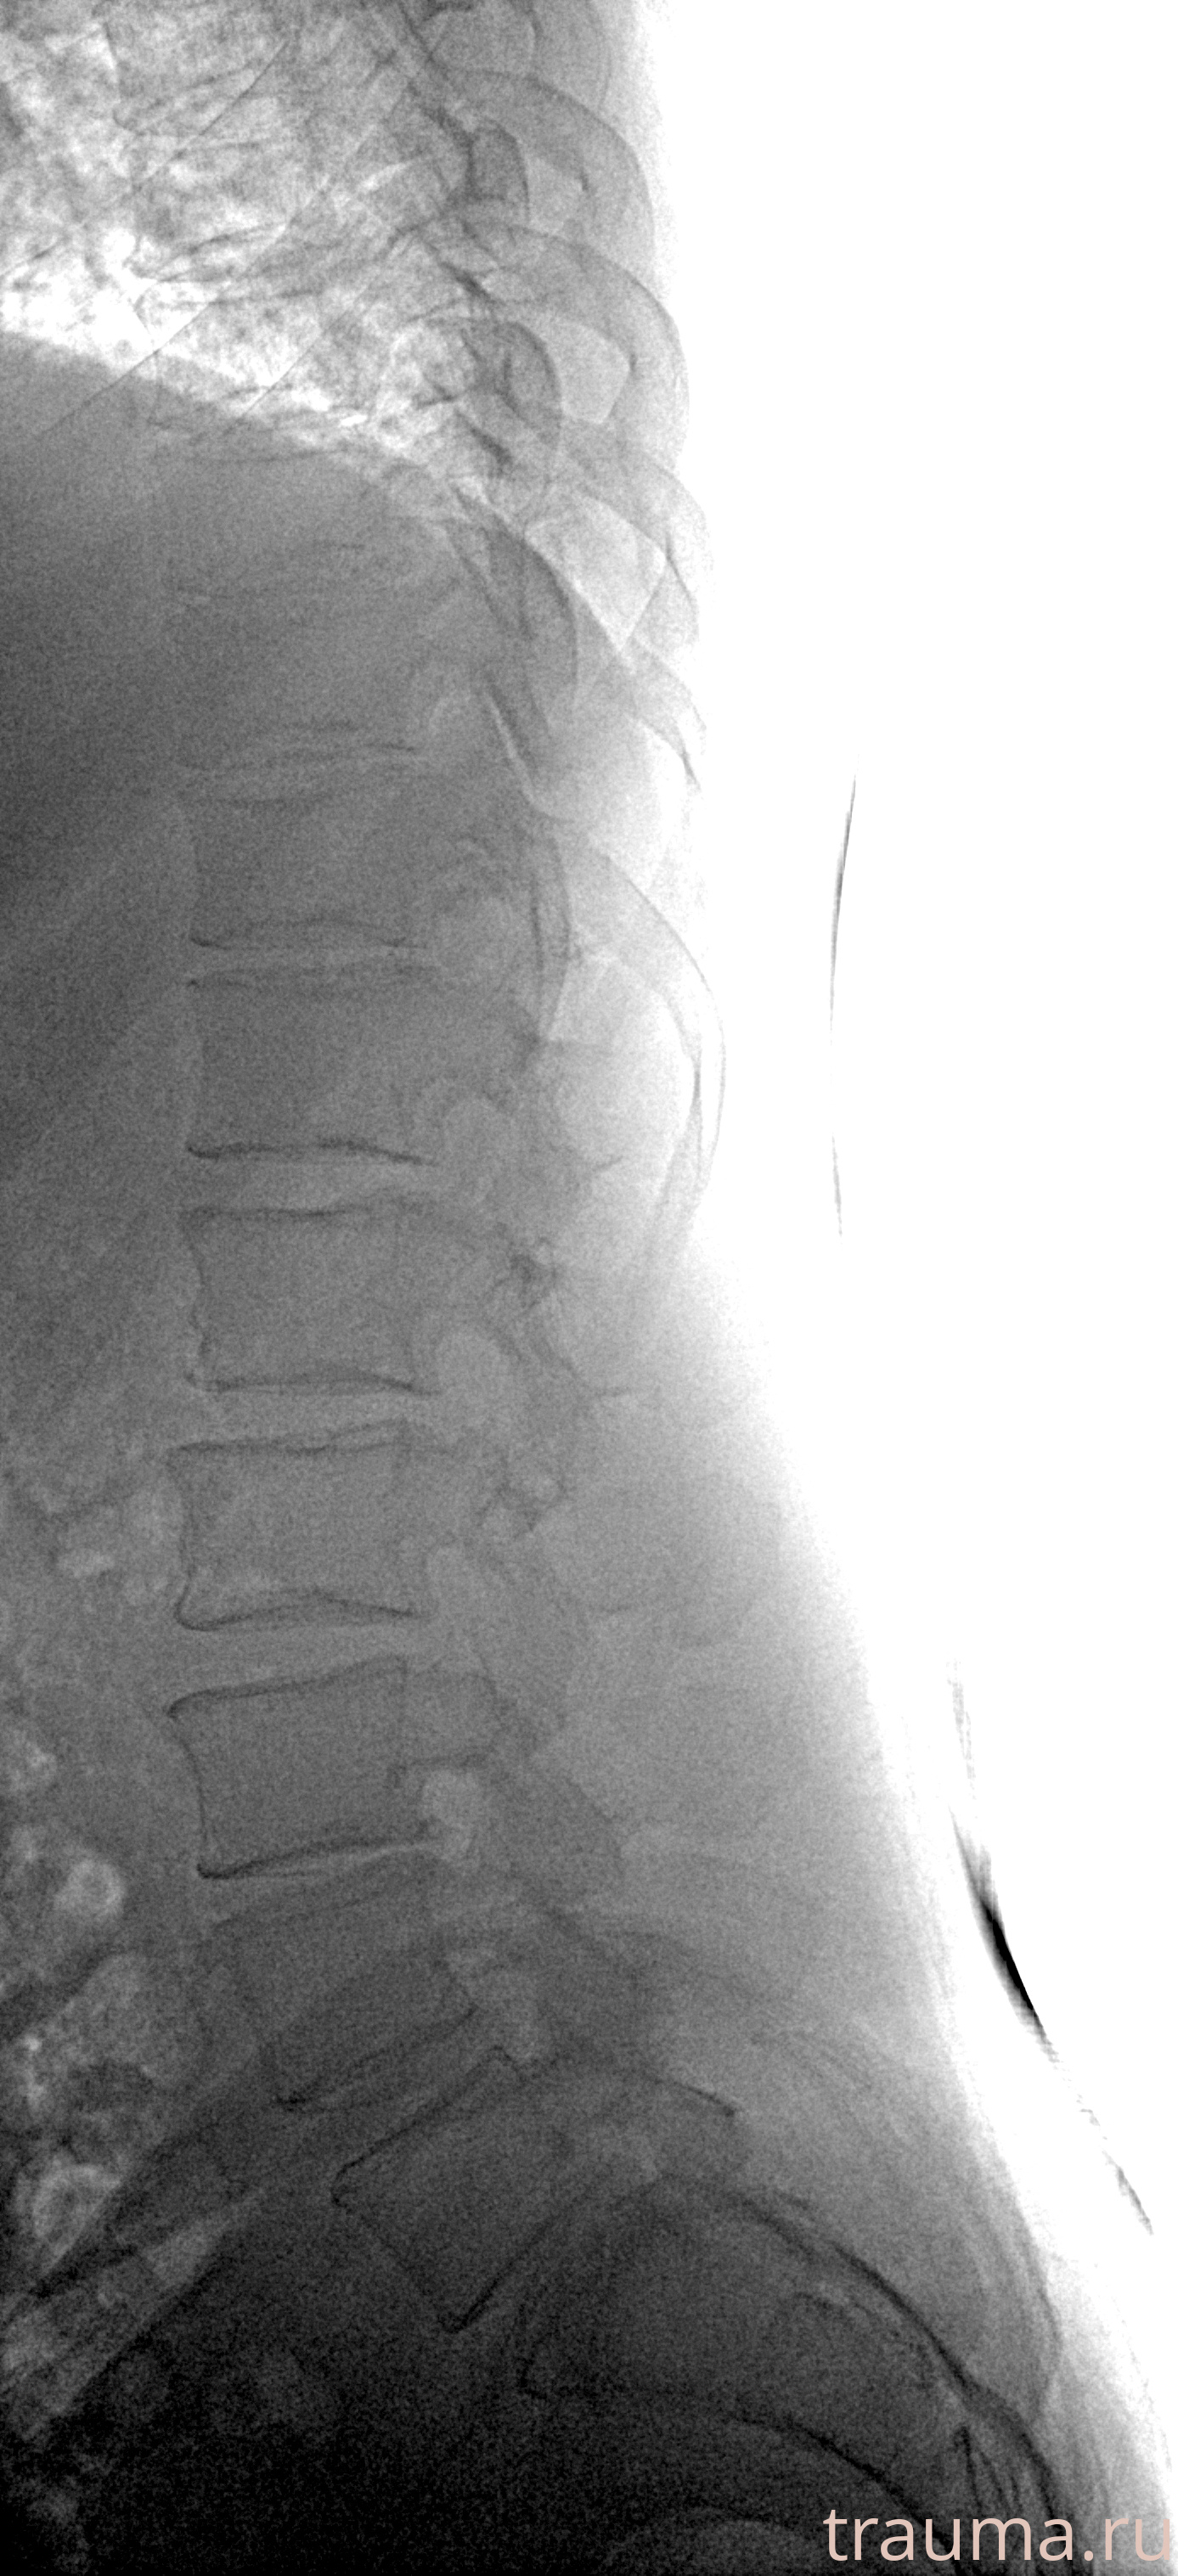

Рентгенограммы

Рентген на дому: по вашему адресу приезжает врач-рентгенолог, травматолог-ортопед с мобильным рентгеновским аппаратом, проводит диагностику травмы или заболевания, делает необходимые рентгенограммы, дает рекомендации по дальнейшему лечению. Получить качественные снимки в домашних условиях возможно благодаря уникальной методике, разработанной МосРентген Центром для института  Склифосовского